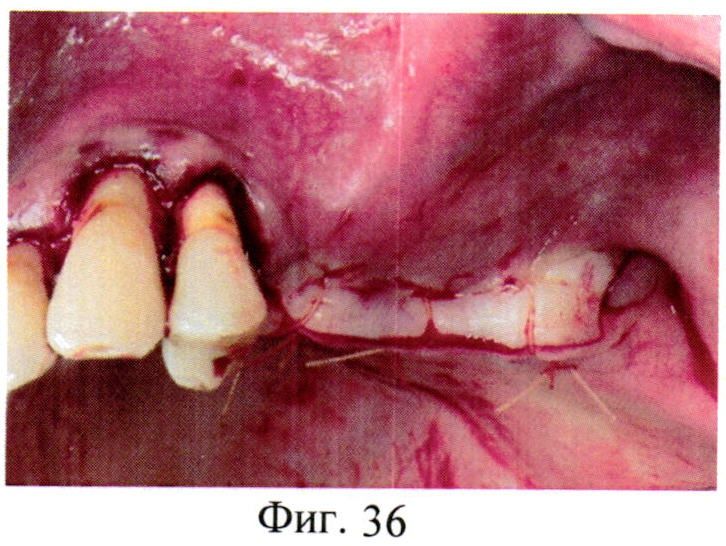

[44]

Пол - мужской, возраст-52 лет, диагноз - Вторичная частичная адентия верхней челюсти слева. Операция - Открытый синуслифтинг с дентальной имплантацией. Операционная рана после поднятия дна верхнечелюстной пазухи и установки трех дентальных имплантов в позиции 25, 26, 27 зубов (сегментарная окклюзионная проекция). Операционная рана после наложения трех базовых «Н-образных» швов, которые создают плотный контакт краев раны по высоте и ширине (сегментарная окклюзионная проекция). Операционная рана после наложения трех базовых «Н-образных» швов - хорошо виден поднимающий эффект «Н-образных» швов. В дополнение к «Н-образным» швам добавлены узловые одиночные швы (сегментарная окклюзионная проекция). Заживление раны на 21-е сутки (сегментарная окклюзионная проекция). См. фиг.34-38.